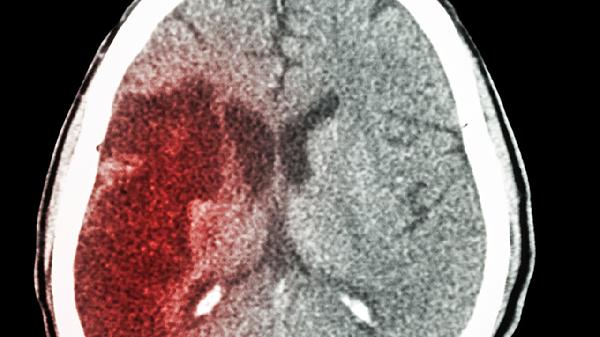

摔跤后脑出血症状主要有头痛、呕吐、意识障碍、肢体无力、瞳孔异常等。脑出血可能与外伤、高血压、脑血管畸形等因素有关,通常表现为上述症状。建议及时就医,积极配合医生治疗。

脑出血患者可能出现瞳孔大小不等、对光反射迟钝或消失等异常表现。瞳孔异常可能与脑疝形成、脑干受压等因素有关。患者可能伴随呼吸循环衰竭等症状。医生可能会紧急进行开颅血肿清除术,并使用甘露醇注射液降低颅内压。